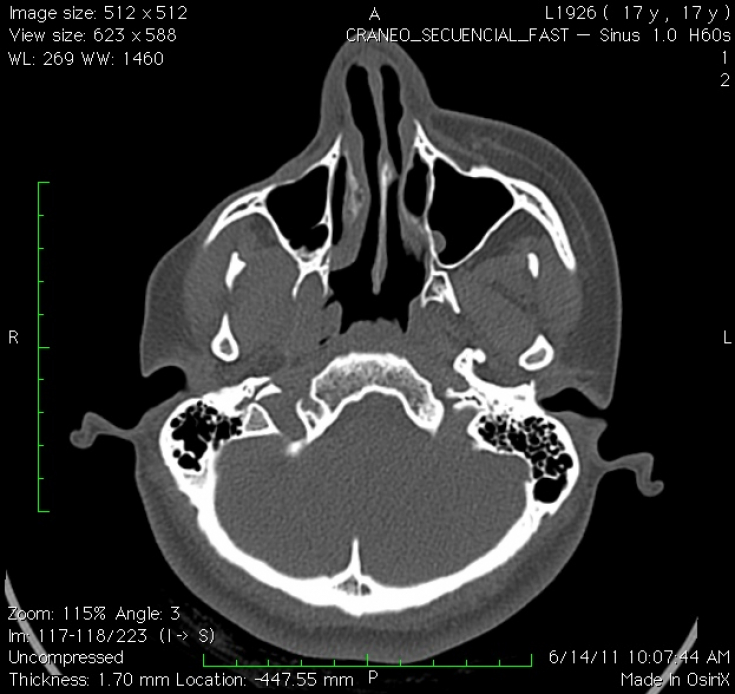

10% of those affected develop a seizure disorder as part of the disease. Epileptic seizures, as a rule, are Jacksonian in nature (characterized by contraction of the muscle group, which subsequently spread to neighboring muscles) and occur on the side opposite the affected side of the face. Half of these cases are associated with abnormalities in both the gray and white matter of the brain — usually ipsilateral, but sometimes contralateral — which are detected during magnetic resonance imaging (MRI) scans.

Enophthalmos (inward displacement of the eyeball) is the most common ocular pathology seen in Parry-Romberg syndrome, which is caused by a decrease in subcutaneous tissue around the orbit. Other manifestations include ptosis, pupillary constriction (miosis), reddening of the conjunctiva, and decreased sweating (anhidrosis) of the affected side of the face.

Diagnosis can be made solely on the basis of the history and physical examination of people who have only facial asymmetry. For those reporting neurological symptoms such as migraine or seizures, brain MRI is the imaging modality of choice. Diagnostic lumbar puncture and serum autoantibody testing may also be indicated. Oligoclonal bands and an elevated IgG index can be detected in 50% of patients.